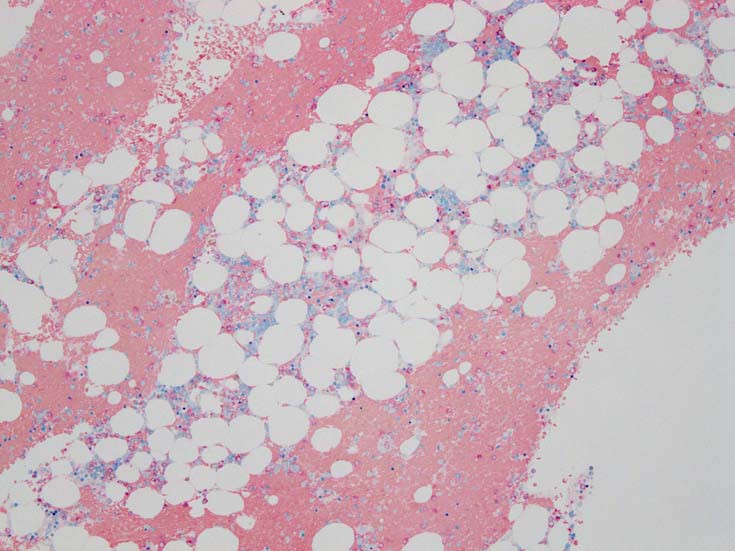

骨髄赤芽球のHbF発現

MDS症例のHbF発現.

サムネイル画像をクリックすると大きな画像が見られます.

MDSでの赤芽球HbF発現は, 陽性細胞はそれほど多くない印象ですが, この低形成性MDS症例では, 多くの陽性細胞がaggregatesを形成していました.